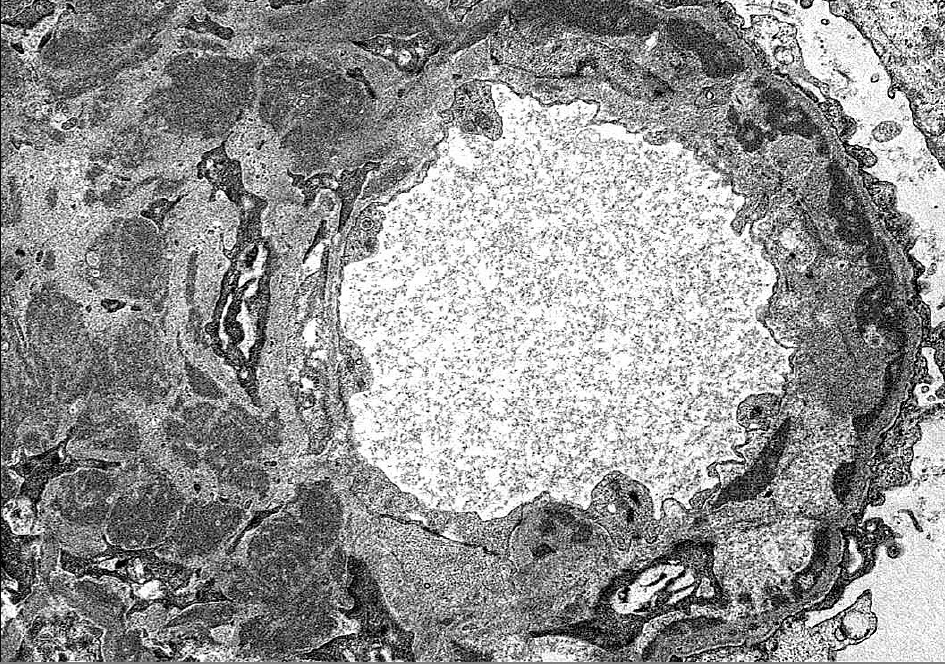

By light microscopy, PGNMID most commonly presents with a membranoproliferative-pattern of injury in both adults [2] and in pediatric patients [3-5], although some patients may show a mesangial proliferative, endocapillary proliferative, or rarely, a membranous pattern of injury [1,2,8] (Figure 1). Crescents may be present in less than a third of cases and are typically focal [2,8]. Immunofluorescence staining in PGNMID characteristically shows a pattern consistent with a complete monoclonal antibody, most commonly IgG-kappa, although lambda light chain restriction may be seen in 27-40% of adult patients [1,2] and in up to three quarters of pediatric patients [5]. Additionally, biopsies with IgM or IgA staining have infrequently been reported [5]. PGNMID demonstrates granular staining in the mesangium and along capillary loops, typically with complement, and infrequently may show a membranous pattern [2,3]. Extraglomerular deposits are not a feature of PGNMID [2]. IgG3 is the most commonly reported IgG subclass in PGNMID, followed by IgG1 and rarely IgG2 [1-5] (Figure 2). No cases of PGNMID with IgG4 deposits have been reported in the literature, which may be helpful in distinguishing PGNMID from other diseases with monoclonal IgG deposits. Electron microscopy is additionally important in distinguishing PGNMID from other glomerulonephritides with monoclonal deposits. The electron dense deposits of PGNMID are granular without the powdery, punctate appearance of those found with light chain, light and heavy chain, or heavy chain deposition disease, and they lack substructure or fibrils [1-3]. Deposits are usually distributed along the subendothelial aspect of glomerular basement membranes (GBMs), within the mesangium, and less extensively along the subepithelial surface of GBMs mirroring the pattern of staining seen by immunofluorescence (Figure 3).

Figure 3. Granular non-Randall-type electron-dense deposits are present throughout the mesangium and along the subendothelial side of glomerular basement membranes with associated cellular interposition. There are no fibrils or substructure to deposits (Electron micrograph, original magnification x6800).